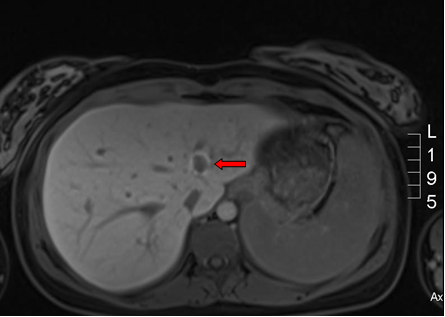

Figure 1. Computed tomography of abdomen and the histology of RCC.

Figure 1: Computed tomography of abdomen and the histology of RCC. A, Axial CT scan of left renal tumor occupying almost half of the abdomen (arrow). B, Coronal CT scan view of left renal tumor at the upper pole displacing the normal lower pole renal parenchyma (arrow). C, Hematoxylin and Eosin staining of the tumor showed a chomophobe morphology with peri-nuclear halo and transitional cells.

A healthy baby girl was delivered via spontaneous vaginal delivery at term. Within a few days postpartum, an abdominal computed tomography scan revealed a large left heterogeneous mass with mixed density and contrast enhancement and a small indeterminate liver lesion (Figures 1 A and B). Open left radical nephrectomy was performed 3 weeks following delivery. Intra-operatively, there was no evidence of metastatic disease and a 2086g left renal tumor measuring 23.0x17.0x13.0 cm3 was successfully removed. The post-operative recovery was uneventful. Pathological analysis revealed chromophobe RCC, pT2bN0M0 with peri-nuclear halo and transitional cells (Figure 1 C). There was no venous infiltration and the tumor was CK7, CD117 positive and CD10 negative with no sarcomatoid or rhabdoid differentiation. Surgical margins were clear. Magnetic resonance imaging at one week post-operation showed a small liver nodule consistent with focal nodular hyperplasia and no appearance of typical metastasis in the liver (Figure 2). On follow up, the patient remained well with no evidence of recurrence or metastases.